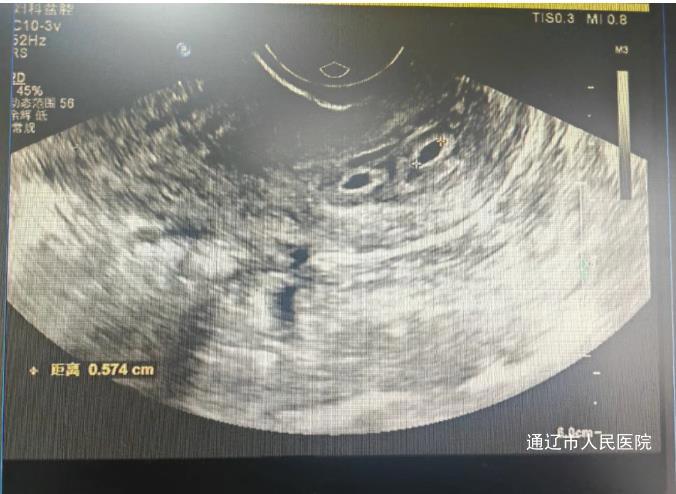

宫颈妊娠因宫颈组织脆弱易引发大出血,严重威胁生命。首例患者为36岁女性,因停经后阴道不规则出血就诊,经检查血β-hCG水平高达5403.8mIU/mL,超声显示宫颈管内异常回声,确诊为宫颈妊娠。另一名27岁患者,因持续4天阴道流血从当地医院转诊,血β-hCG水平达11436mIU/mL,彩超提示宫颈内口妊娠。

确诊后,主任医师李艳春、白鹏来迅速启动多学科会诊,制定腹腔镜下子宫动脉阻断术+宫腔镜辅助下宫颈妊娠组织清除术的治疗方案。妇产科、超声医学科、麻醉科、输血科等科室迅速联动,超声医学科主任吕凤精准定位着床部位,麻醉科医生常红军全程评估风险,手术团队历经数小时紧张操作,成功清除病灶并保留生育功能。术后护理团队密切监测病情,辅以心理疏导,患者血β-hCG水平降至正常,超声显示病灶显著缩小,均康复出院。